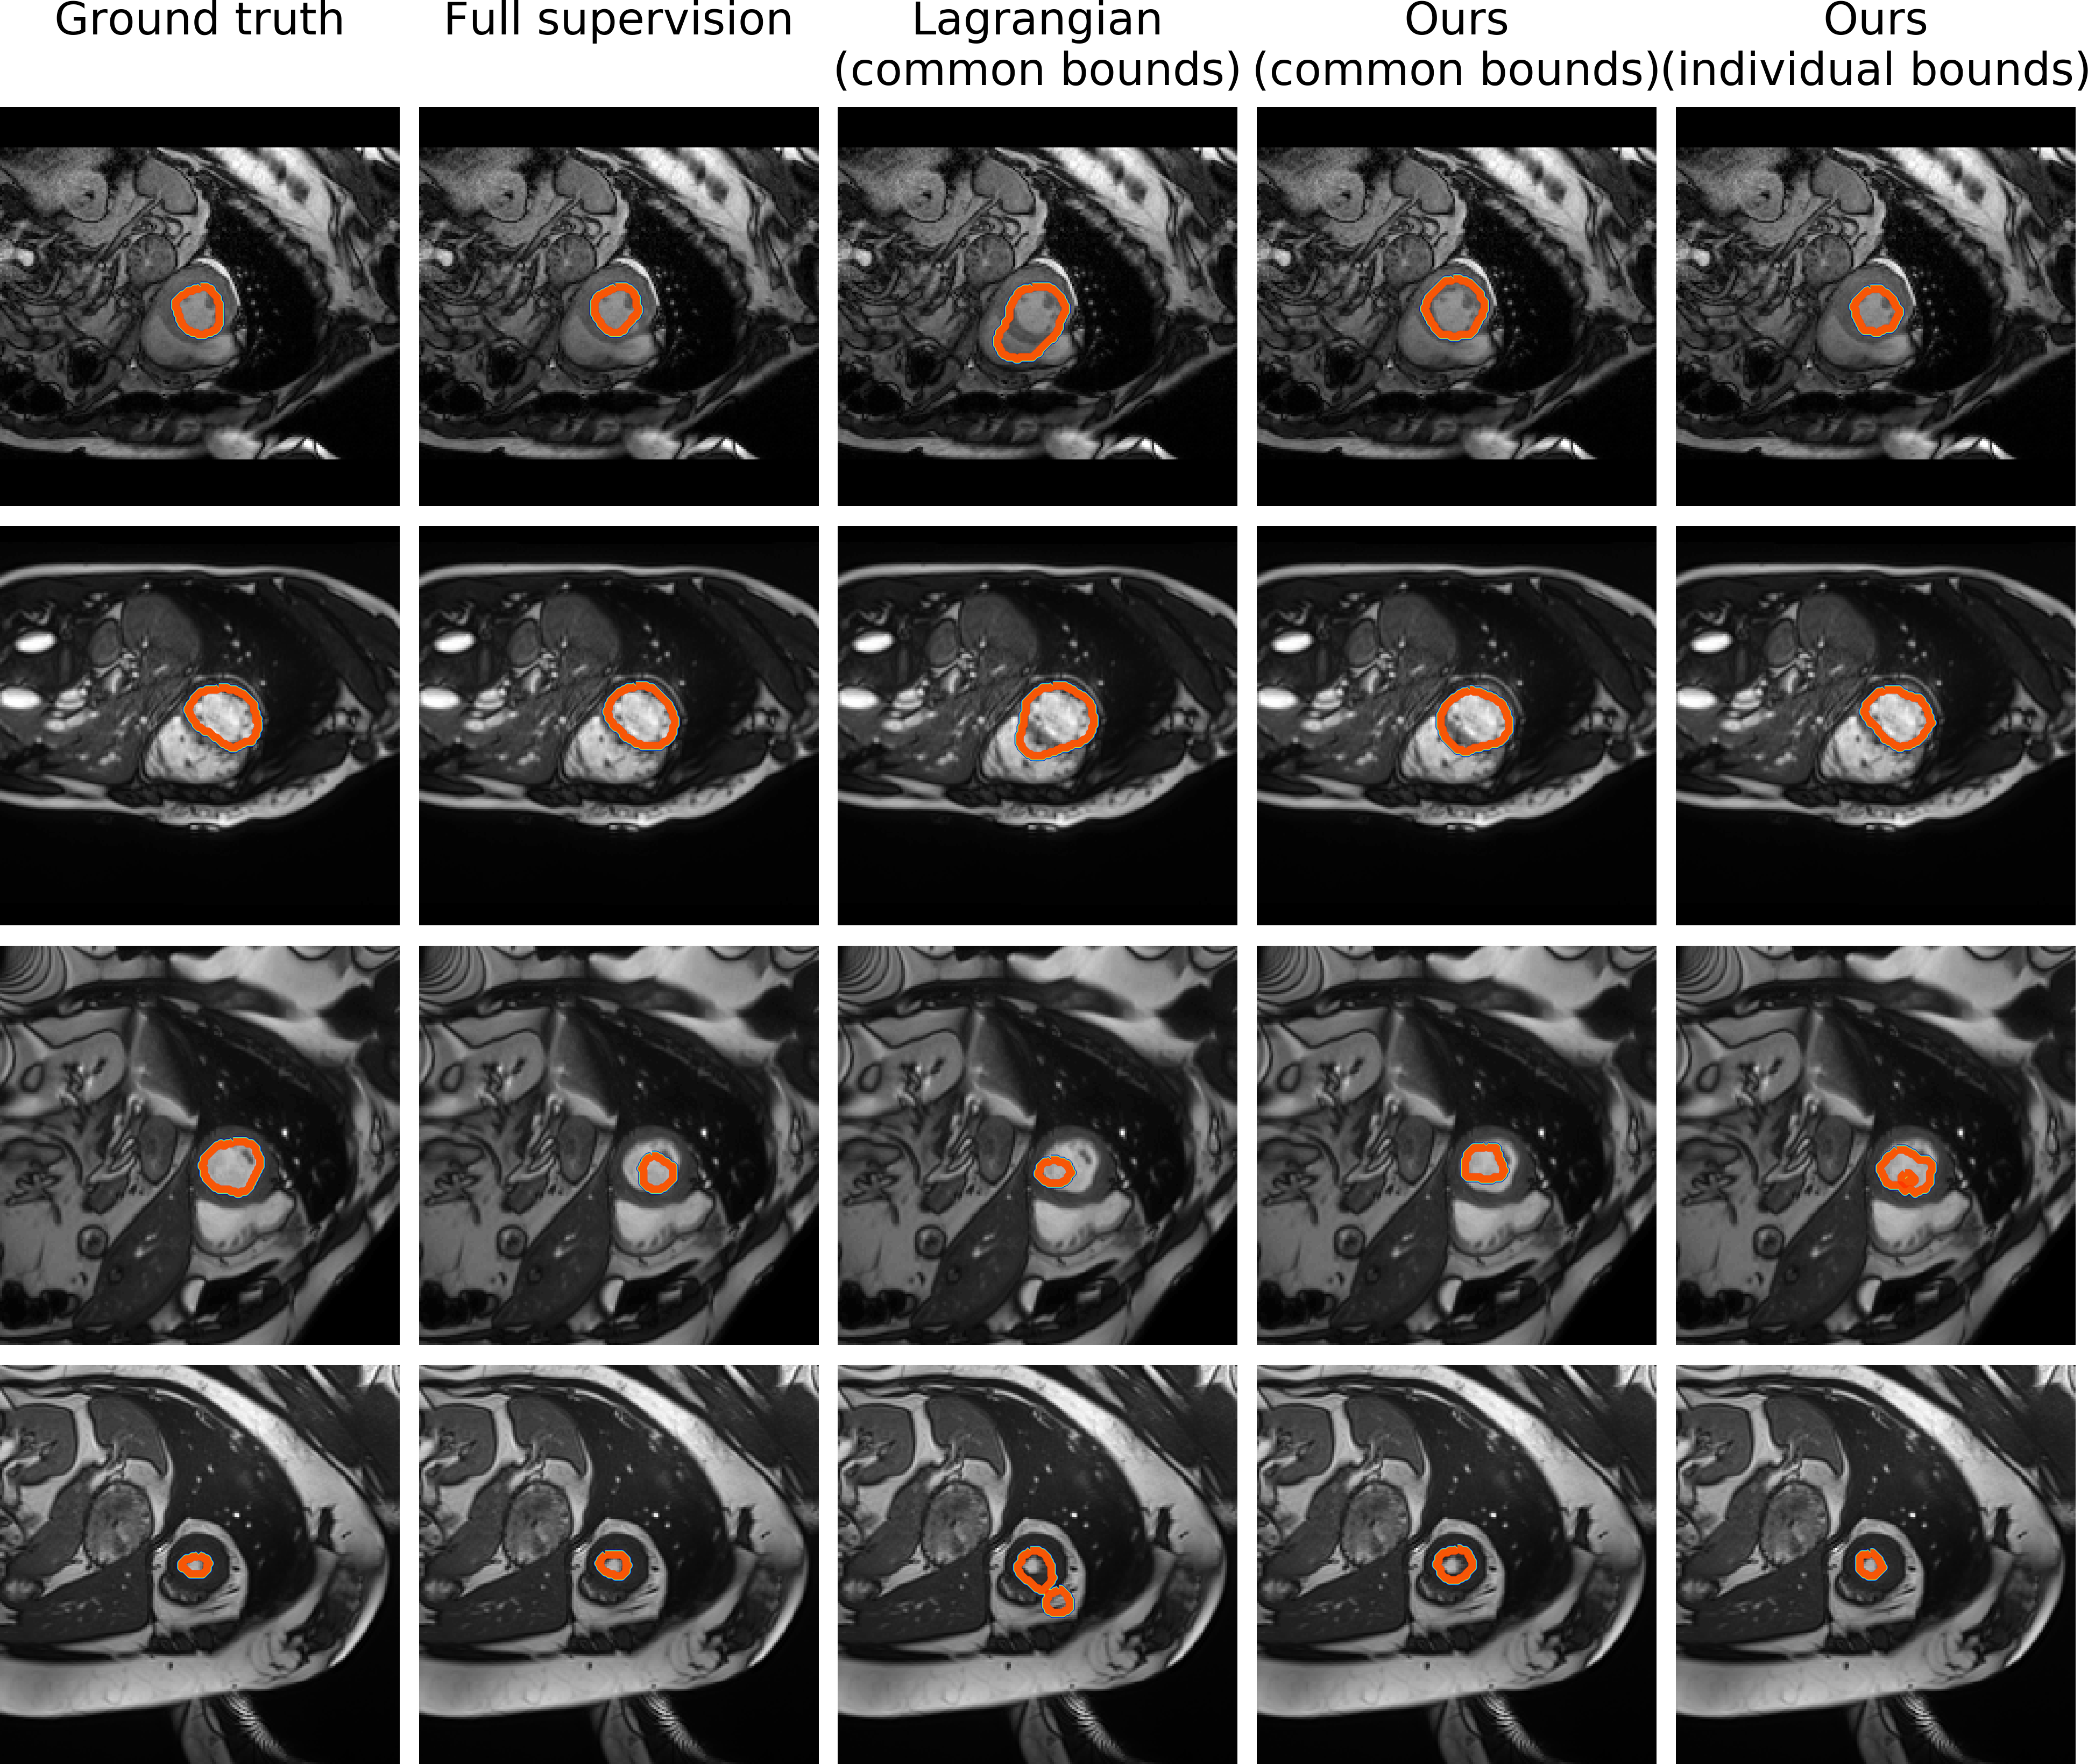

Prostate segmentation task

As in the previous case, we depict the results of full supervision, tag bounds, common bounds and individual bounds. Both the tags and common bounds locate the object in a similar fashion, but both have difficulties finding a precise contour, typically over-segmenting the target region. This is easily explained by the variability of the organ and the very low contrast on some images. As shown in the last column, using individual bounds greatly improves the results.

Refer to caption

Figure 7: Qualitative comparison of the different levels of supervision. Each row represents a 2D slice from different scans. (Best viewed in colors)